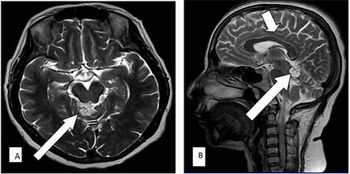

Case History: 15-month-old with focal seizure, developmental delay, disproportionate increase in size of head.

Published: January 10th 2017 | Updated: